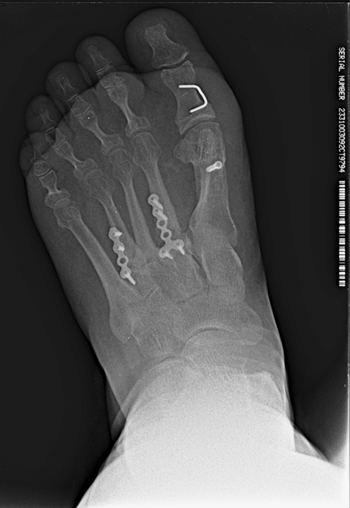

Se realizó radiografía dorso-plantar en carga del pie derecho (Figura 1) que mostraba una imagen radiológica compatible con ausencia de consolidación de las osteotomías en las bases de 2.º, 3.º y 4.º metatarsianos, además de la presencia de hallux abductus valgus. Se solicitó una tomografía axial computarizada (TAC) para estudiar más detenidamente el estado actual del proceso de consolidación ósea. La paciente acudió con resultado de TAC el 5 de mayo de 2015, donde se evidenció la ausencia completa de consolidación ósea en segundo metatarsiano (Figuras 2A y 2B), consolidación prácticamente completa de tercer metatarsiano (Figura 2C) y la presencia de callo óseo con consolidación incompleta en el cuatro metatarsiano (Figura 2D).

Figura 1. Radiografía dorso-plantar en carga del pie derecho. Se evidencia la ausencia de consolidación de las osteotomías en las bases de 2.º, 3.º y 4.º metatarsianos después de 9 meses de la intervención inicial.

Figura 5. Imagen postoperatoria tras la cirugía.